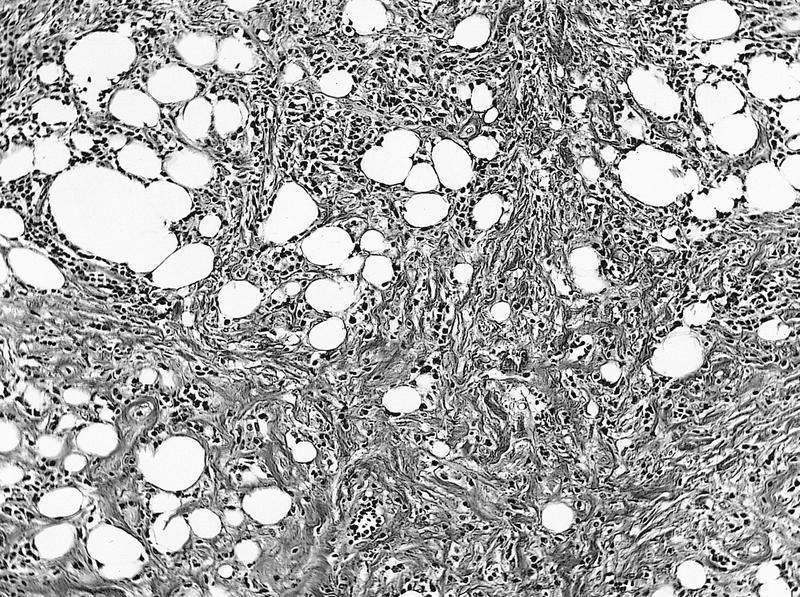

Microscopic (histologic) description

Microscopic (histologic) images

AFIP images

Microscopic (histologic) description

- General:

- Edematous tissue with excessive production of ground substance, chronic inflammatory cells, vascular proliferation and hyperplastic connective tissue

- May have periphlebitis with tissue eosinophilia

- Inflammatory myofibroblastic tumor:

- Combinations of fibroblasts and myofibroblasts in background of plasma cells and other inflammatory cells

Microscopic (histologic) images

AFIP images